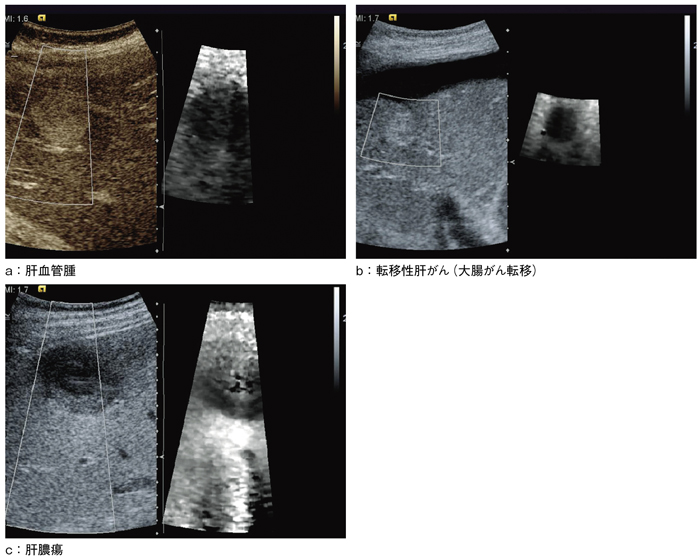

臨床応用例を図4に示す。

図4 VTTIによる臨床例